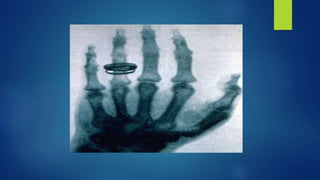

 USÓ PLACAS FOTOGRÁFICAS, PARA DEMOSTRAR QUE LOS OBJETOS

DE SU ESPESOR Y REALIZÓ LA PRIMERA RADIOGRAFÍA HUMANA,

USANDO LA MANO DE SU MUJER. LOS LLAMÓ "RAYOS INCÓGNITA",

 USÓ PLACASFOTOGRÁFICAS, PARA DEMOSTRAR QUE LOS OBJETOS ERAN MÁS O MENOS TRANSPARENTES A LOS RAYOS X DEPENDIENDO DE SU ESPESOR Y REALIZÓ LA PRIMERA RADIOGRAFÍA HUMANA, USANDO LA MANO DE SU MUJER. LOS LLAMÓ "RAYOS INCÓGNITA", O "RAYOS X" PORQUE NO SABÍA QUÉ ERAN, SOLO QUE ERAN GENERADOS POR LOS RAYOS CATÓDICOS AL CHOCAR CONTRA CIERTOS MATERIALES. PESE A LOS DESCUBRIMIENTOS POSTERIORES SOBRE LA NATURALEZA DEL FENÓMENO, SE DECIDIÓ QUE CONSERVARAN ESE NOMBRE.